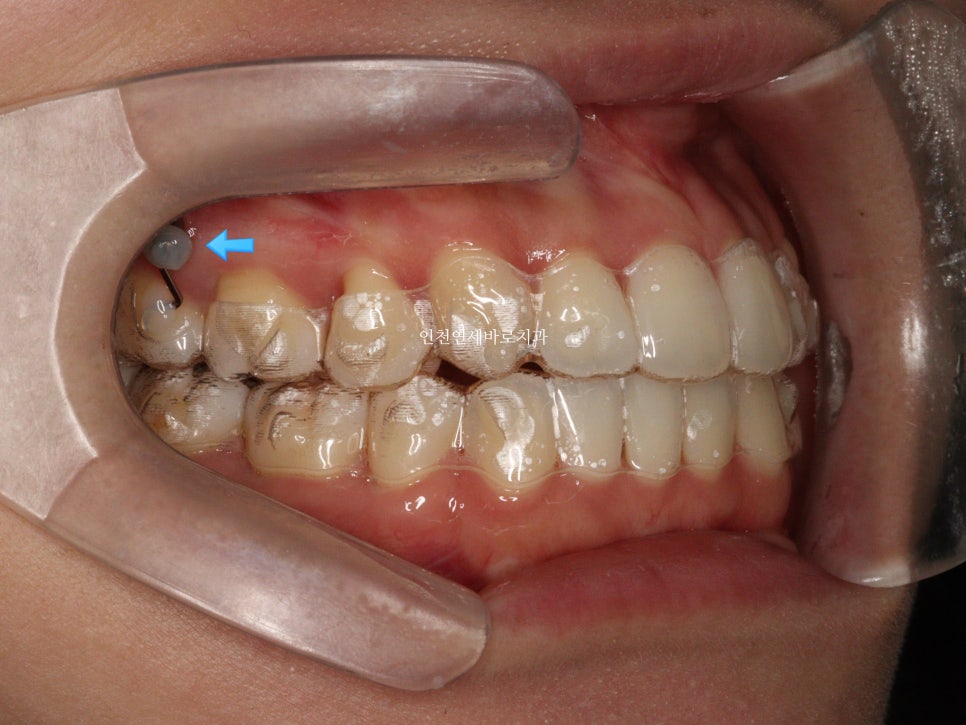

선천적결손치아가 있던 환자분이며, 웃을때 사진을 보면 약간의 비대칭도 관찰됩니다.

아래 앞니가 없다보니 중심선도 안맞고, 아래 치아의 사이즈도 양쪽이 다름을 알 수 있습니다.

비대칭이 있다보니 위쪽 치아가 전체적으로 기울어져 있는것도 확인됩니다.

악궁확장장치 #mse 도 사용하였습니다.

이후 #인비절라인 으로 치료를 시작했습니다. 그때가 2020.6.30.